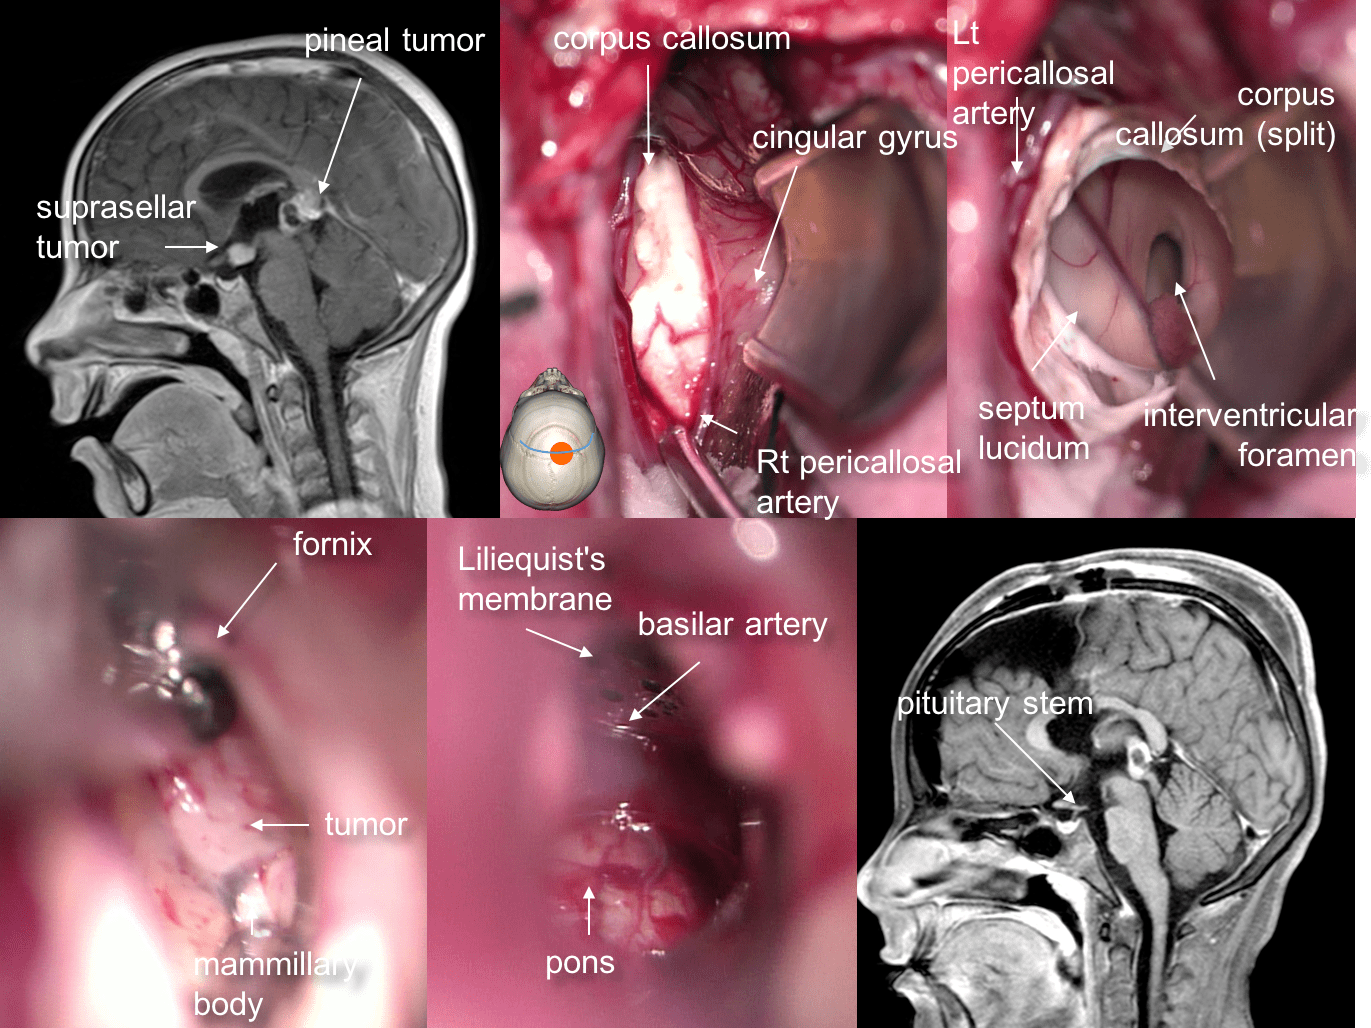

cette chirurgie concerne les craniopharyngiomes, gliomes opto-chiasmatiques et tumeurs germinales supra-sellaires, ainsi que les « grosses tiges pituitaires ».

selon que leur extension de fait vers le haut (troisième ventricule), l’avant (étage antérieur) latéralement (bandelette optique, incisure tentorielle) ou vers le bas (sinus sphénoïdal), les tumeurs supra-sellaires pourront être abordées par voie :

- sous-frontale

- transventriculaire

- ptérionale

- trans-sphénoïdale

la résection des tumeurs partant de la tige (craniopharyngiomes, tumeur germinales) permet rarement le respect anatomique de cette dernière, encore moins de conserver une tige pituitaire fonctionnelle ; les principaux objectifs sont la résection tumorale et le respect des voies optiques et de l’hypothalamus.

il s’agit d’une voie transcalleuse étendue à la région suprasellaire. c’est don ici également une voie d’abord médiane.

elle est utile en cas de tumeur à développement intra-ventriculaire prédominant, en particulier les tératomes supra-sellaires. c’est une voie utile en urgence devant une hydrocéphalie tumorale aiguë, s’il n’est pas possible de faire une fenestration endoscopique. c’est également la voie d’abord pour les hamartomes hypothalamiques.

la voie ptérionale

elle est adaptée pour l’abord des tumeurs limitées de la tige pituitaire (grosse tige pituitaire) à visée biopsique, plus difficilement de résection (débulking de gliomes opte-chiasmatiques). elle est également facilitée par l’existence d’un kyste volumineux (cf. ci-dessous)

avantages

c’est une voie plus limitée que la voie sous-frontale, elle n’interfère pas avec les nerfs olfactifs ; elle permet de contrôler des lésions s’étendant latéralement : le long de la bandelette optique (zone aveugle dans la chirurgie par voie sous-frontale) et sous la tente du cervelet.

inconvénients

c’est un abord unilatéral, qui permet malgré tout un contrôle bilatéral, mais le principal inconvénient est le risque de lésion vasculaire : spasme, possibilité d’anévrysme fusiforme de l’axe carotidien, possiblement par ischémie de la paroi artérielle, lésion des vaisseaux perforants.